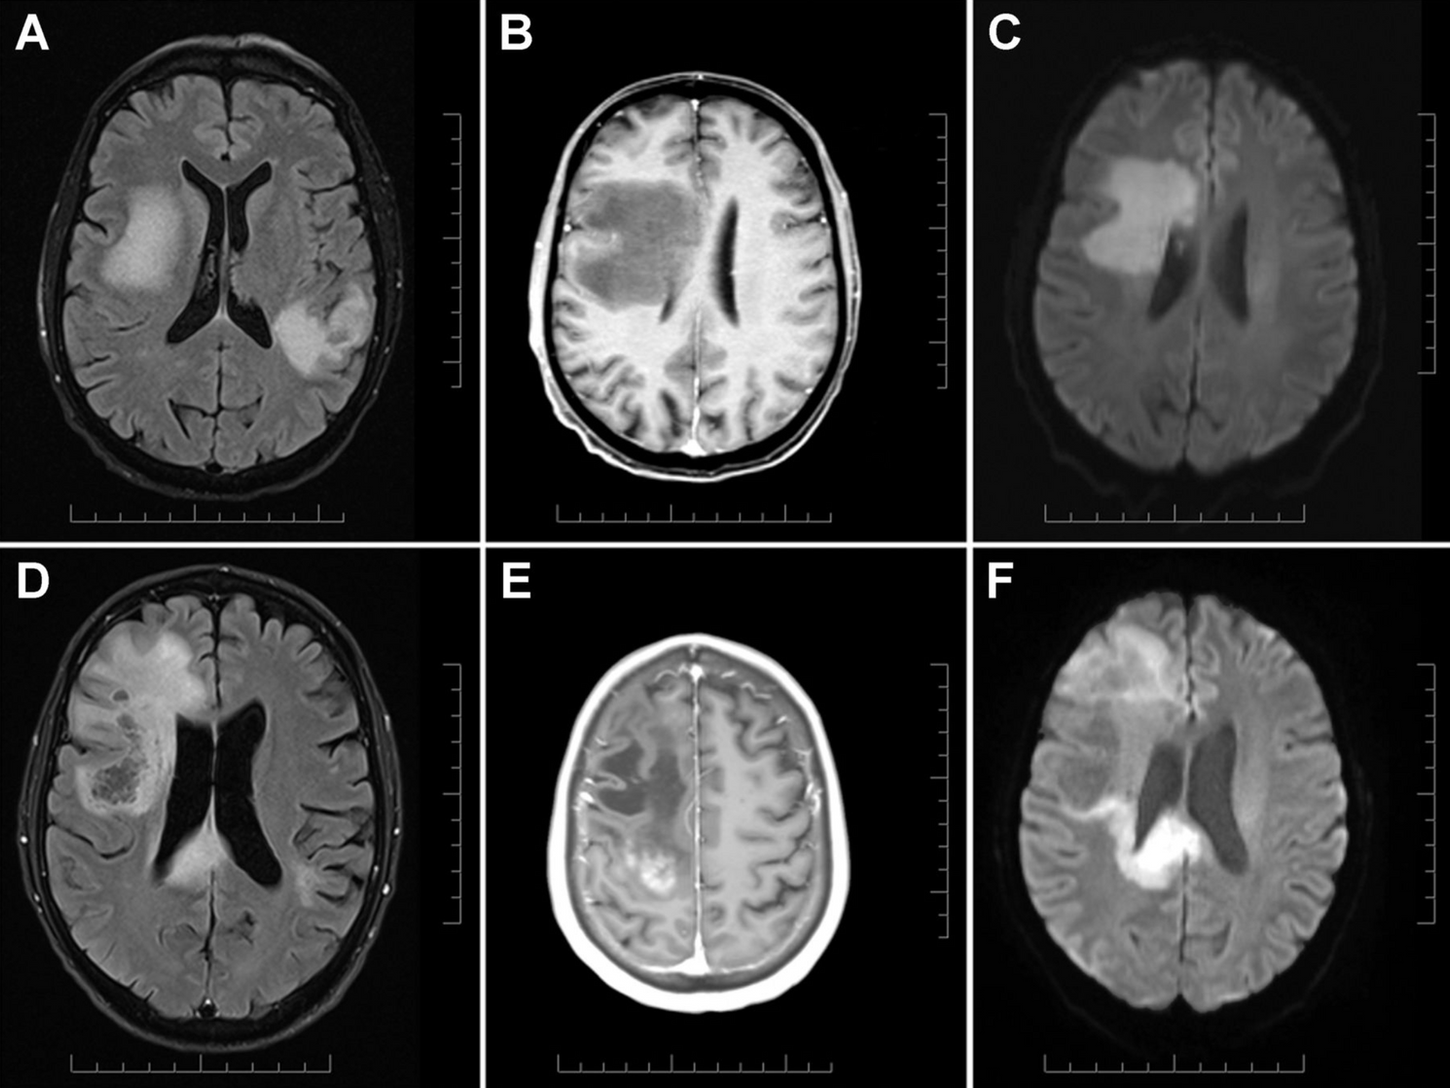

Rosai-Dorfman Disease of the CNS

Reversible Small Vessel Vasculitis and Encephalitis in HIV Antiretroviral Resistance

Subacute CNS Demyelination after Treatment with Nivolumab for Melanoma

Eosinophilic CNS vasculitis can mimic demyelinating disease of the brain and spinal cord